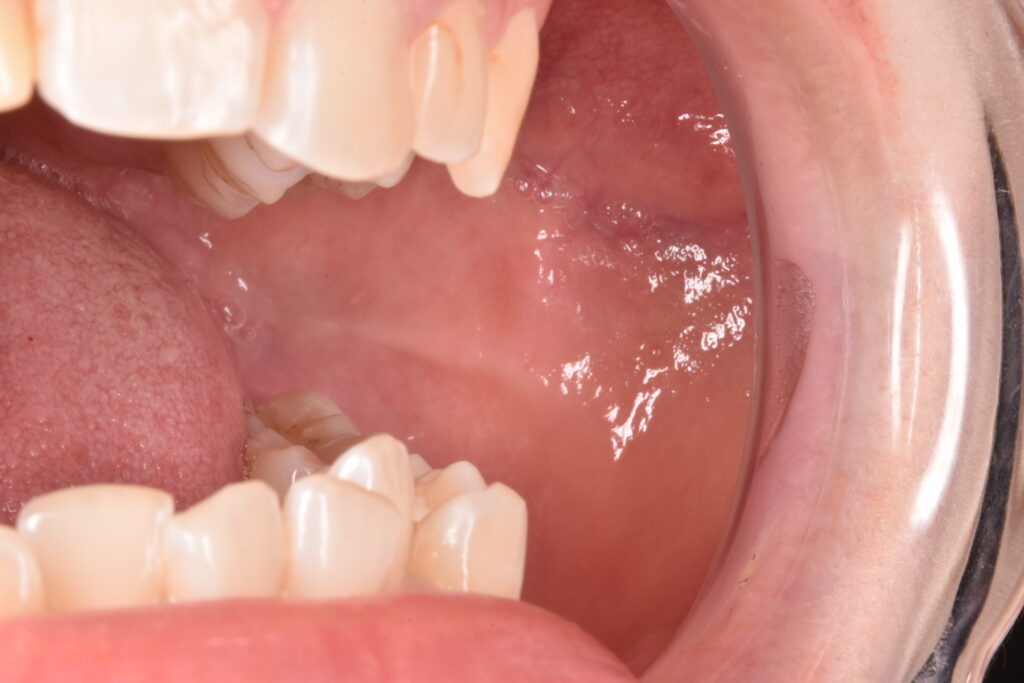

バッカルファット除去後2週間

内出血もなく腫れもほとんど気にならないと仰っていました。また術前は週に1回は頬の肉を噛んでいたが今は1回も噛まなくなったし顔の輪郭も少し細くなった程度であまり変わらず希望通りと仰ってくださいました。